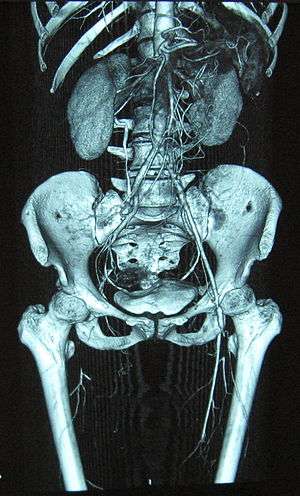

Angiograms of the upper and lower extremities can be helpful in making the diagnosis of Buerger’s disease. In the proper clinical setting, certain angiographic findings are diagnostic of Buerger’s. These findings include a “corkscrew” appearance of arteries that result from vascular damage, particularly the arteries in the region of the wrists and ankles. Collateral circulation gives "tree root" or "spider leg" appearance.[1] Angiograms may also show occlusions (blockages) or stenosis (narrowings) in multiple areas of both the arms and legs. Distal plethysmography also yields useful information about circulatory status in digits. To rule out other forms of vasculitis (by excluding involvement of vascular regions atypical for Buerger’s), it is sometimes necessary to perform angiograms of other body regions (e.g., a mesenteric angiogram).